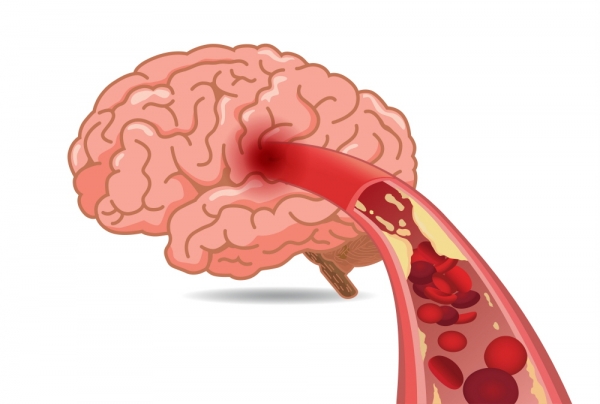

뇌혈류 감소가 일정 시간 이상 계속되면 뇌조직의 괴사가 시작되어요. 뇌조직이 괴사 되어 회복 불가능한 상태에 이르렀을 때 이를 뇌경색이라고하고요. 반면 뇌혈류 감소에 의해 뇌기능에 이상이 생겼지만, 적절한 치료를 통해 넉넉한 뇌혈류가 다시 보급되어 뇌조직의 괴사 없이 뇌기능이 회복된 경우를 일과성 허혈성 발작이라고 불리워요. 허혈성 뇌졸중은 뇌경색과 일괄성 허혈성 발작을 모두 다 포함해서서 일컫는 용어이예요.

뇌조직은 평소에도 거량 물량의 피를 공급받고 있고요. 근데 수많은 이유으로 인해서 뇌혈관에 혈관 등을 이루는 관이 막히는 경우가 일으켜서 뇌에 공급되는 혈액량이 줄어들게 보면 뇌조직이 기능을 정확히 하지 못하게 돼요.

동맥경화증을 방지하기 위하여 콜레스테롤이 높은 식품은 피하며, 가공음식, 인스턴트음식 또한 가급적 지양하고 염분의 양이 많은 식품은 피해요. 또한 금연, 금주하며, 고혈압과 뇌졸중 예방을 위해서 염분 섭취를 감소시키는 것이 중요해요. 그리고 연쇄적인 운동으로 혈압을 느슨하게하고 비만을 방지해요.